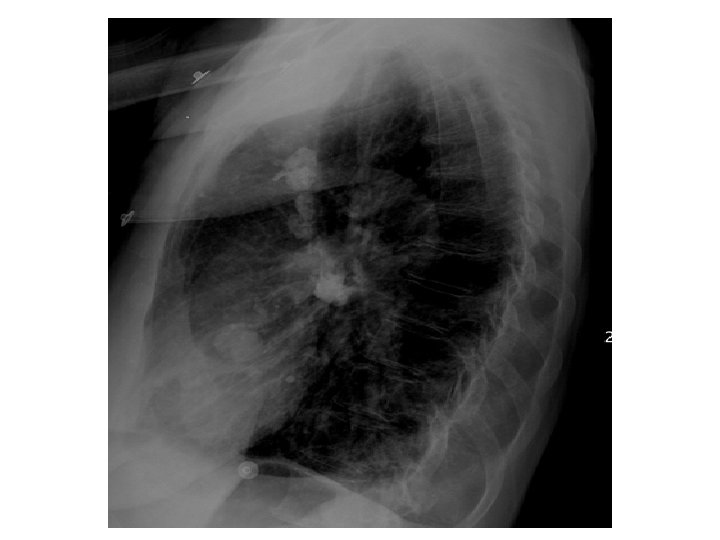

Case History 65 year old male with shortness of breath. Images: PA and Lateral View of the chest. CT of the Chest with IV contrast presented in lung windows. Please note that the images proceed from left to right and top to bottom.

Findings and Differentials Findings: The frontal view of the chest shows multiple prominent tubular structures arising from the right hilum and coursing inferiorly adjacent to the right heart border. There are multiple dilated tubular structures seen in the right lung on CT. Tubular structures within the lung are either vascular or bronchial. If bronchial, they would have to be filled with inspissated mucus to be opaque. But there are bronchi seen adjacent to these tubular structures and the bronchi are normal. The tubular structures therefore represent dilated pulmonary arteries and veins. The remainder of the right lung is normal. There also several calcified lymph nodes from prior granulomatous disease. The cardiac silhouette is normal. There are no pleural effusions. Differential: • Total Anomalous Pumonary Venous Return • Pulmonary AVM • Scimitar Syndrome

Discussion These findings are diagnostic of pulmonary AVMs are believed to be congenital defects in the terminal capillary loops that result in dilatation and formation of vascular sacs. 40 -65 percent of patients with pulmonary AVMs also have AVMs elsewhere (skin, CNS, solid organs). AVMs are seen in Osler-Weber-Rendu disease. Pumonary AVMs appear on imaging as vascular masses adjacent to the pleura or the bronchovascular bundles. They are common in the lower lobes. The draining veins are usually larger in size compared to the feeding arteries. They usually do not cause symptoms but can cause hemoptysis. Due to the right to left shunting, pulmonary AVMs are associated with cerebral abscesses. The right to left shunting also decreases the Pa. O 2 and causes the cardiac output to increase. Angiography is seldom needed to diagnose the condition. The CT findings of multiple dilated pulmonary vessels clinches the diagnosis. It is important to show the feeding artery and draining vein. Catheter embolization is the preferred treatment modality. Dilated bronchi filled with inspissated mucus can mimic this condition.